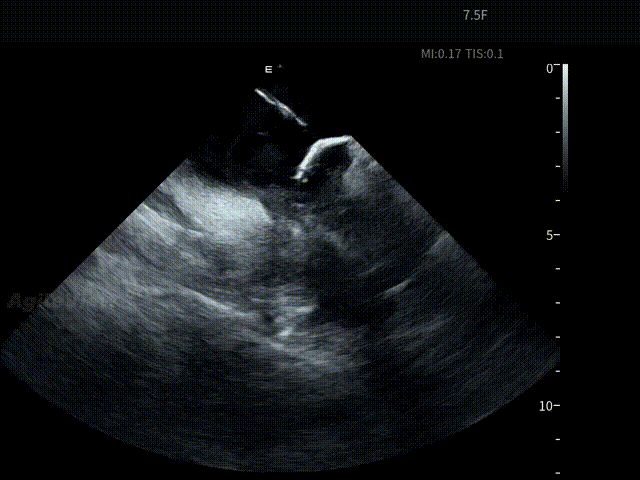

术中,基于AgileView™ 7.5Fr全球最细直径ICE导管的产品优势,周纬教授选择将ICE送入左房,以便更好地进行冷冻球囊的贴靠与位置的判断,在AgileView™ ICE实时影像的指导下, Arctic Front Advance Pro冷冻球囊导管消融导管安全进入左心房,先后完成双侧肺静脉隔离及顶部线隔离, ICE下可见导管贴靠良好,整个消融过程顺利,消融时间仅约25分钟,得益于超声设备清晰的成像质量,在顶部线隔离的时候可借助多普勒模式清晰的观察到球囊与组织的贴靠程度。 整个手术流程在ICE影像的指引下顺利完成,术中患者耐受良好,生命体征保持平稳。

球囊充气

球囊复温后“Blood Bubble”